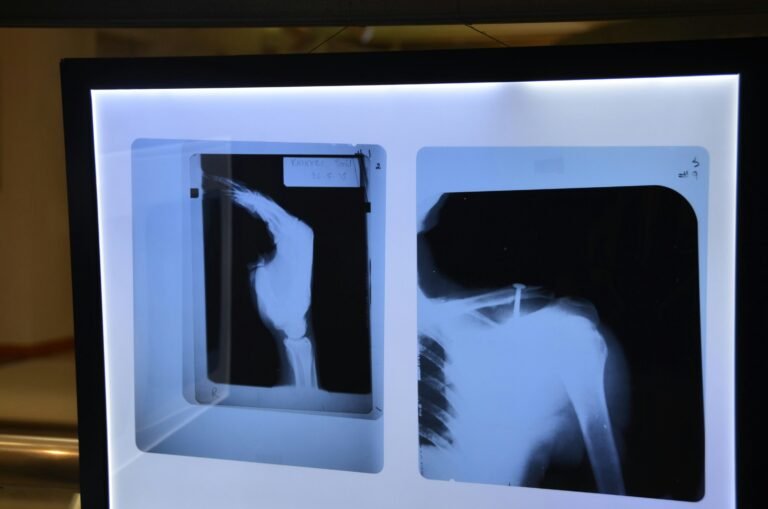

Condições médicas específicas também devem ser consideradas nas análises sobre a dor nas costas. A hérnia de disco, por exemplo, ocorre quando o material gelatinoso no interior de um disco vertebral se projeta para fora, pressionando nervos e causando dor. A artrose, que envolve o desgaste das articulações, é outra causa comum que afeta a mobilidade e provoca desconforto. Problemas musculares também podem resultar em dor aguda ou crônica, assim como condições renais que, em alguns casos, se manifestam como dor referida nas costas.